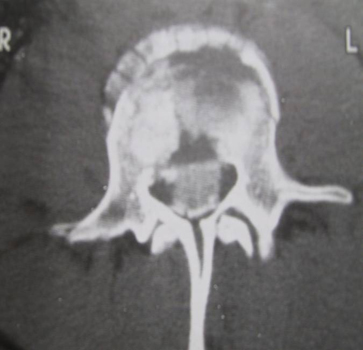

- CT spine